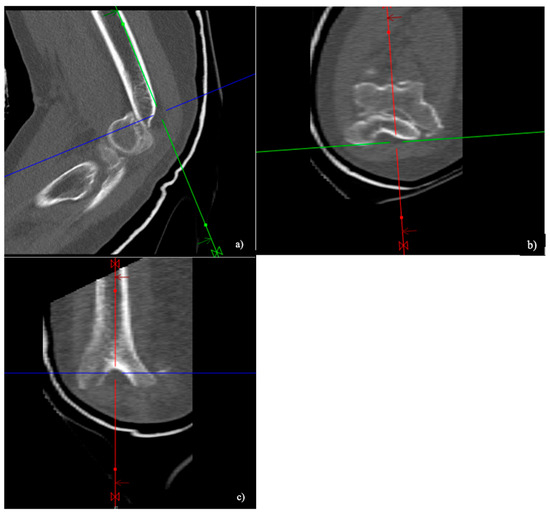

2.3. Conventional CT

2.4. CT Image Analysis

3.5. Complications